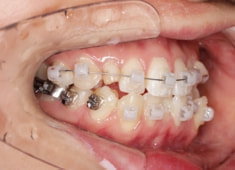

治療開始時

治療中